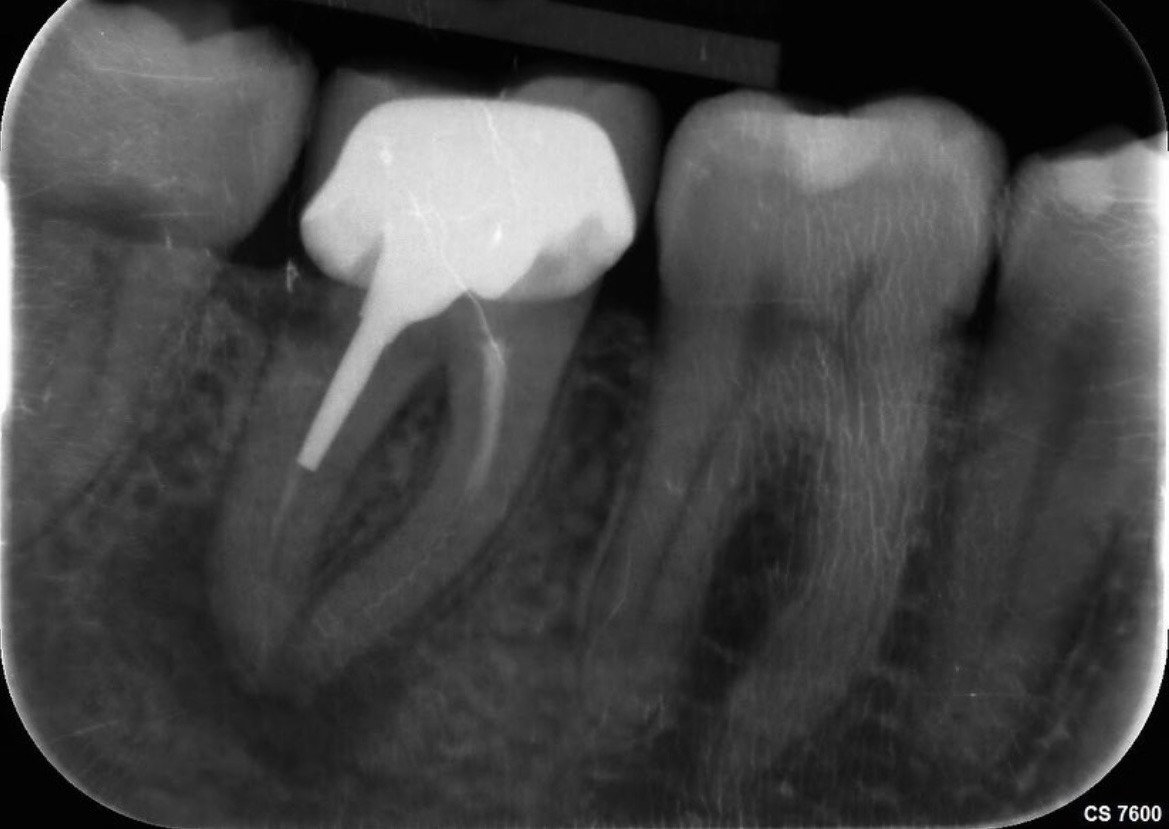

3. L’examen microscopique de la dent et l’imagerie médicale complètent si besoin le diagnostic clinique, notamment en cas d’obturation préalable sur une dévitalisation imparfaite. Nous sommes équipés d’un matériel haut-de-gamme permettant des diagnostics très précis (radiographie, Cône Beam, microscope, …) ;

• vérification de la qualité de l’obturation par radiographie haute définition.

Une dévitalisation se traduit par la suppression des tissus enflammés/infectés, en nettoyant les canaux situés à l’intérieur de la dent de toutes les bactéries et les débris organiques. Une fois désinfectés, ces canaux sont remplis d’un matériau biocompatible qui va assurer leur étanchéité parfaite et empêcher une nouvelle infection. La dévitalisation ne donne pas une dent “morte”, elle la rend simplement insensible. Il faut donc veiller à conserver sa vitalité, avec notamment un parodonte sain.